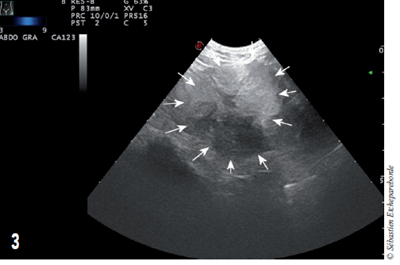

photo 9